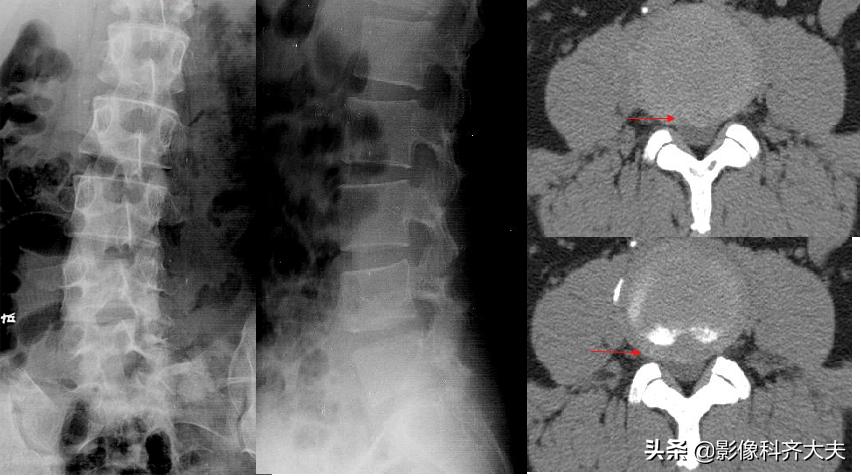

正侧位示腰4、5间隙变窄,CT扫描示腰4、5间盘突出

CT:椎间盘突出(中央型)